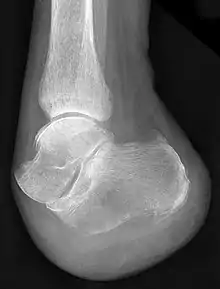

François Chopart est notamment connu pour avoir mis au point une technique d'amputation, longtemps appliquée sur les champs de bataille, consistant à sectionner le pied non pas à travers l'os, mais en suivant les articulations talo-naviculaire et calcanéo-cuboïdienne (qui ont d'ailleurs été regroupées sous la dénomination d'articulation de Chopart en hommage au chirurgien).